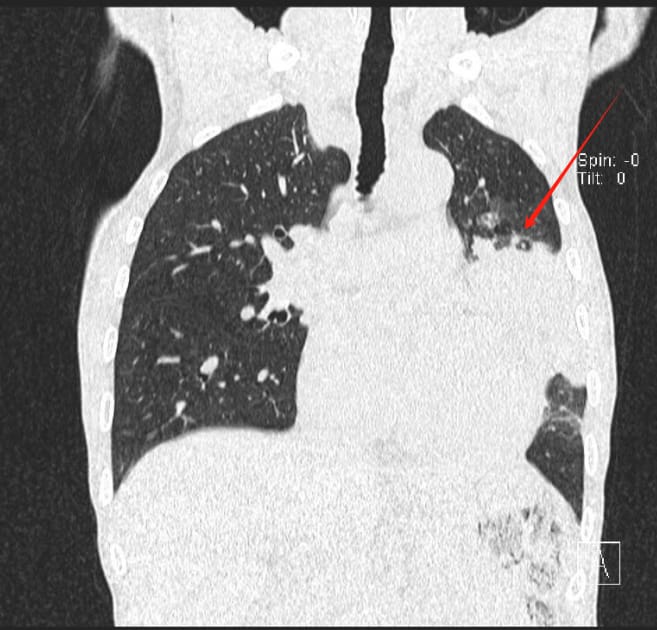

入院后,医生为患者安排了详细的胸部CT扫描。结果显示,其左肺上叶出现了团块状的异常高密度影,部分支气管被堵塞,且有不均匀的强化表现。影像学专家初步判断,这很可能是一种肿瘤性病变。此外,CT还发现颈部椎体可能存在转移灶,这预示着病情的复杂性。

图1 胸部CT影像揭示左肺上叶的肿瘤性病变